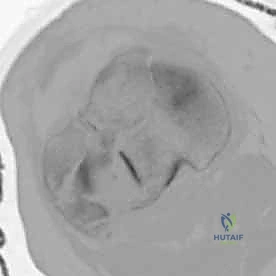

3. الأشعة المقطعية المحوسبة (CT Scan) - المعيار الذهبي

لا يمكن إجراء جراحة لكسر ثنائي اللقمة دون إجراء أشعة مقطعية (يفضل مع إعادة بناء ثلاثية الأبعاد 3D).

* توفر الأشعة المقطعية خريطة دقيقة لكل شظية عظمية.

* تحدد مقدار الانخساف في السطح المفصلي بالمليمتر.

* تكشف الشظايا المخفية، خاصة في الجزء الخلفي من الركبة (Posterior Coronally oriented fragments) والتي تتطلب خطة جراحية خاصة لتثبيتها.